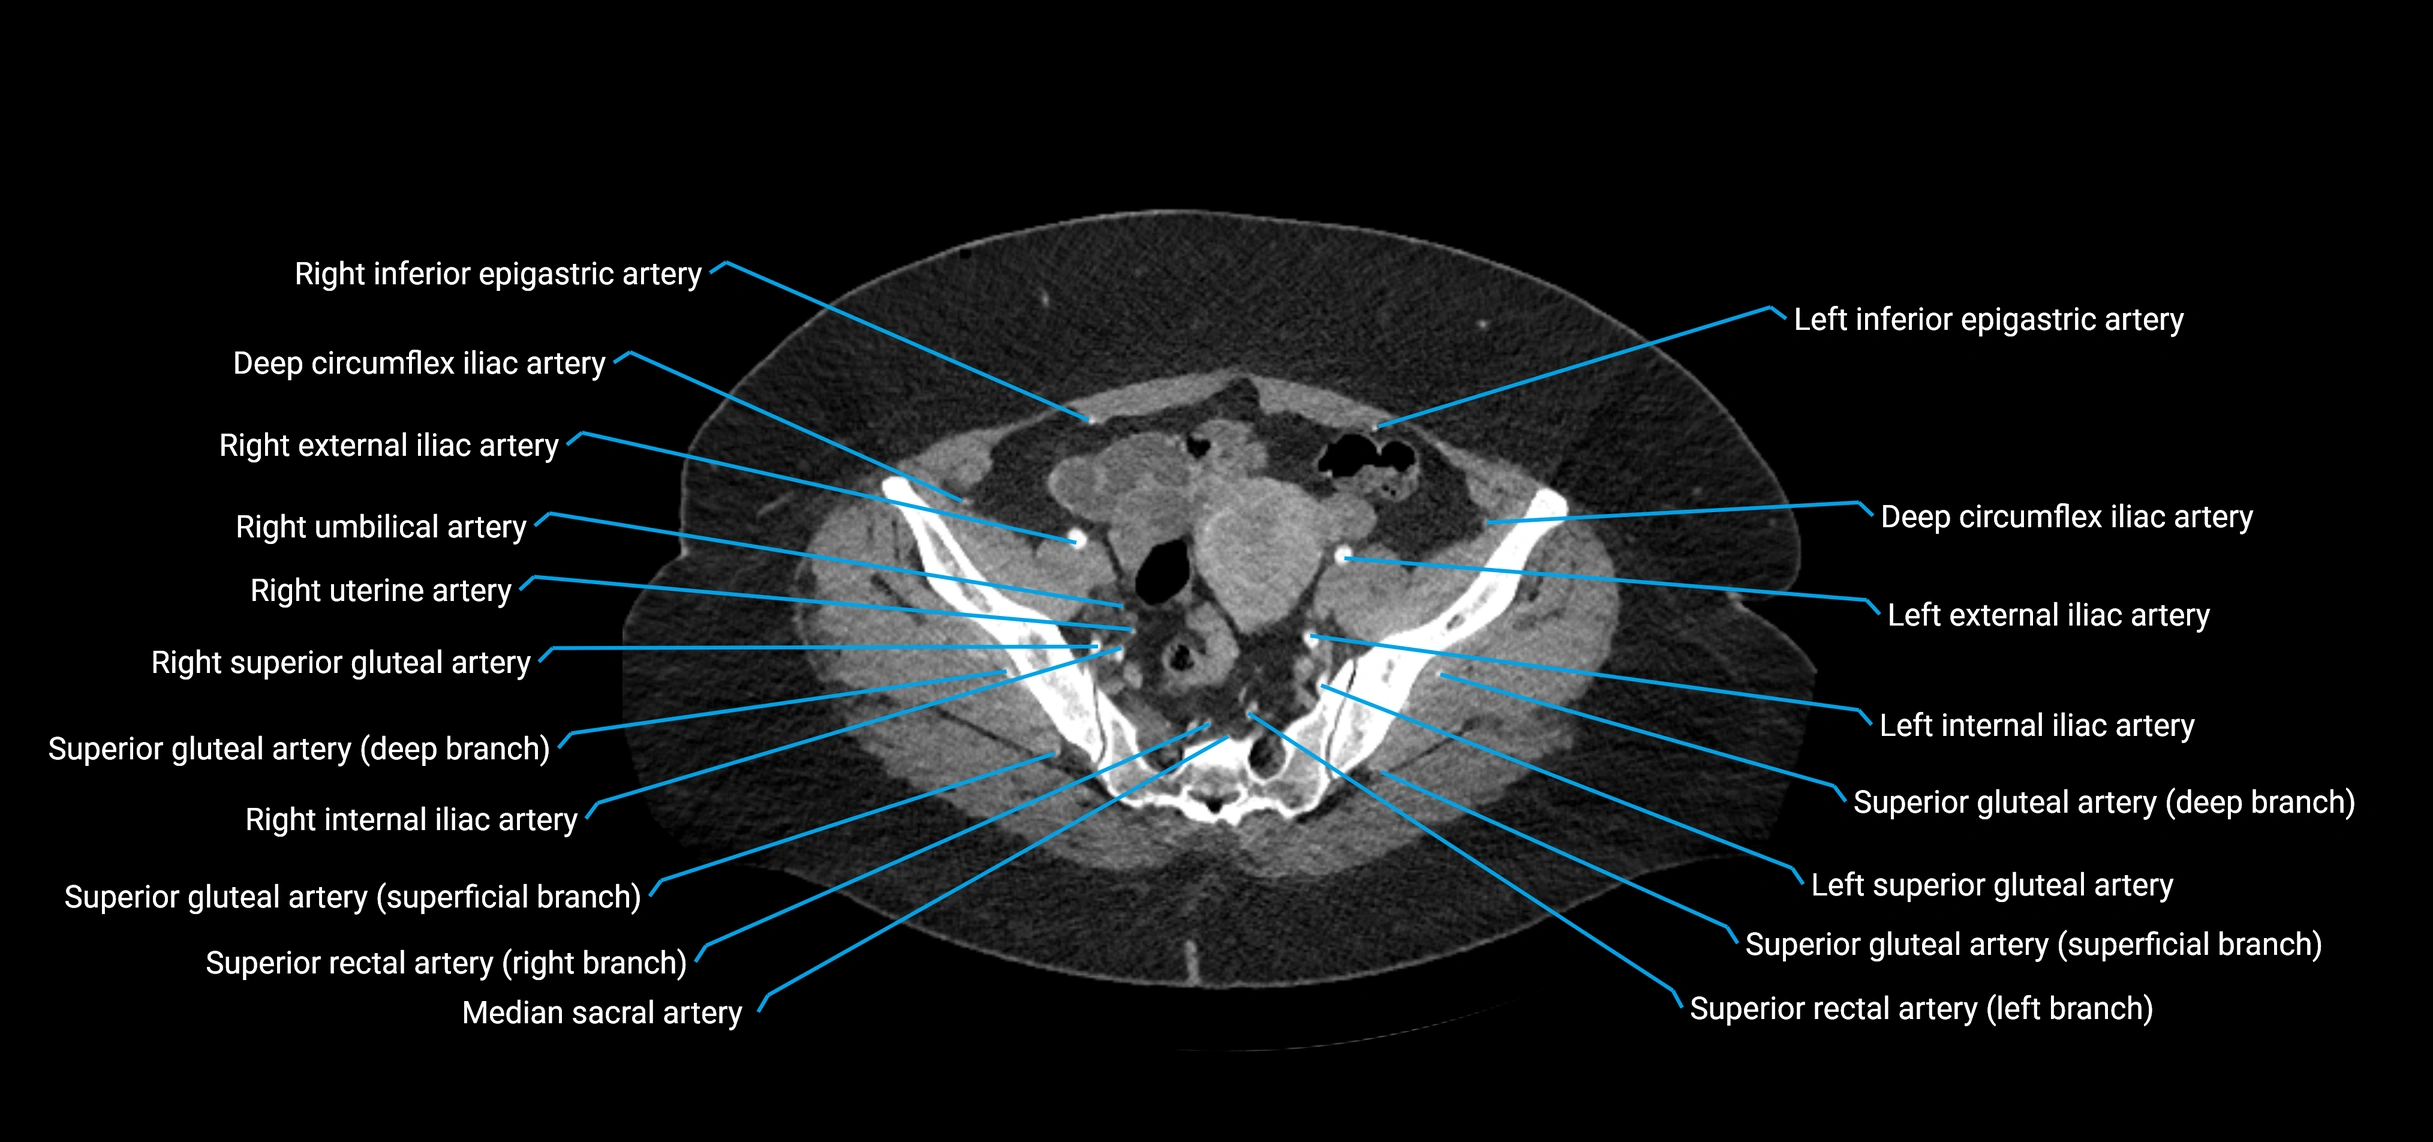

CT images

image

Contrast-enhanced CT (CTA):

• Gold standard for abdominal aortic imaging

• Provides excellent detail of lumen, wall, aneurysm, thrombus, and branch vessels

• Multiplanar and 3D reconstructions help in aneurysm measurement, stent graft planning, and dissection evaluation